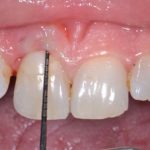

Trattamento di lesioni orali erosive bilaterali di tipo simil-lichenoide con olio ozonizzato

Si riporta il caso di una paziente affetta da lesioni orali simil-lichenoidi persistenti in cui il trattamento con olio ozonizzato si è mostrato estremamente utile, favorendo una drastica riduzione del dolore e delle dimensioni delle lesioni.